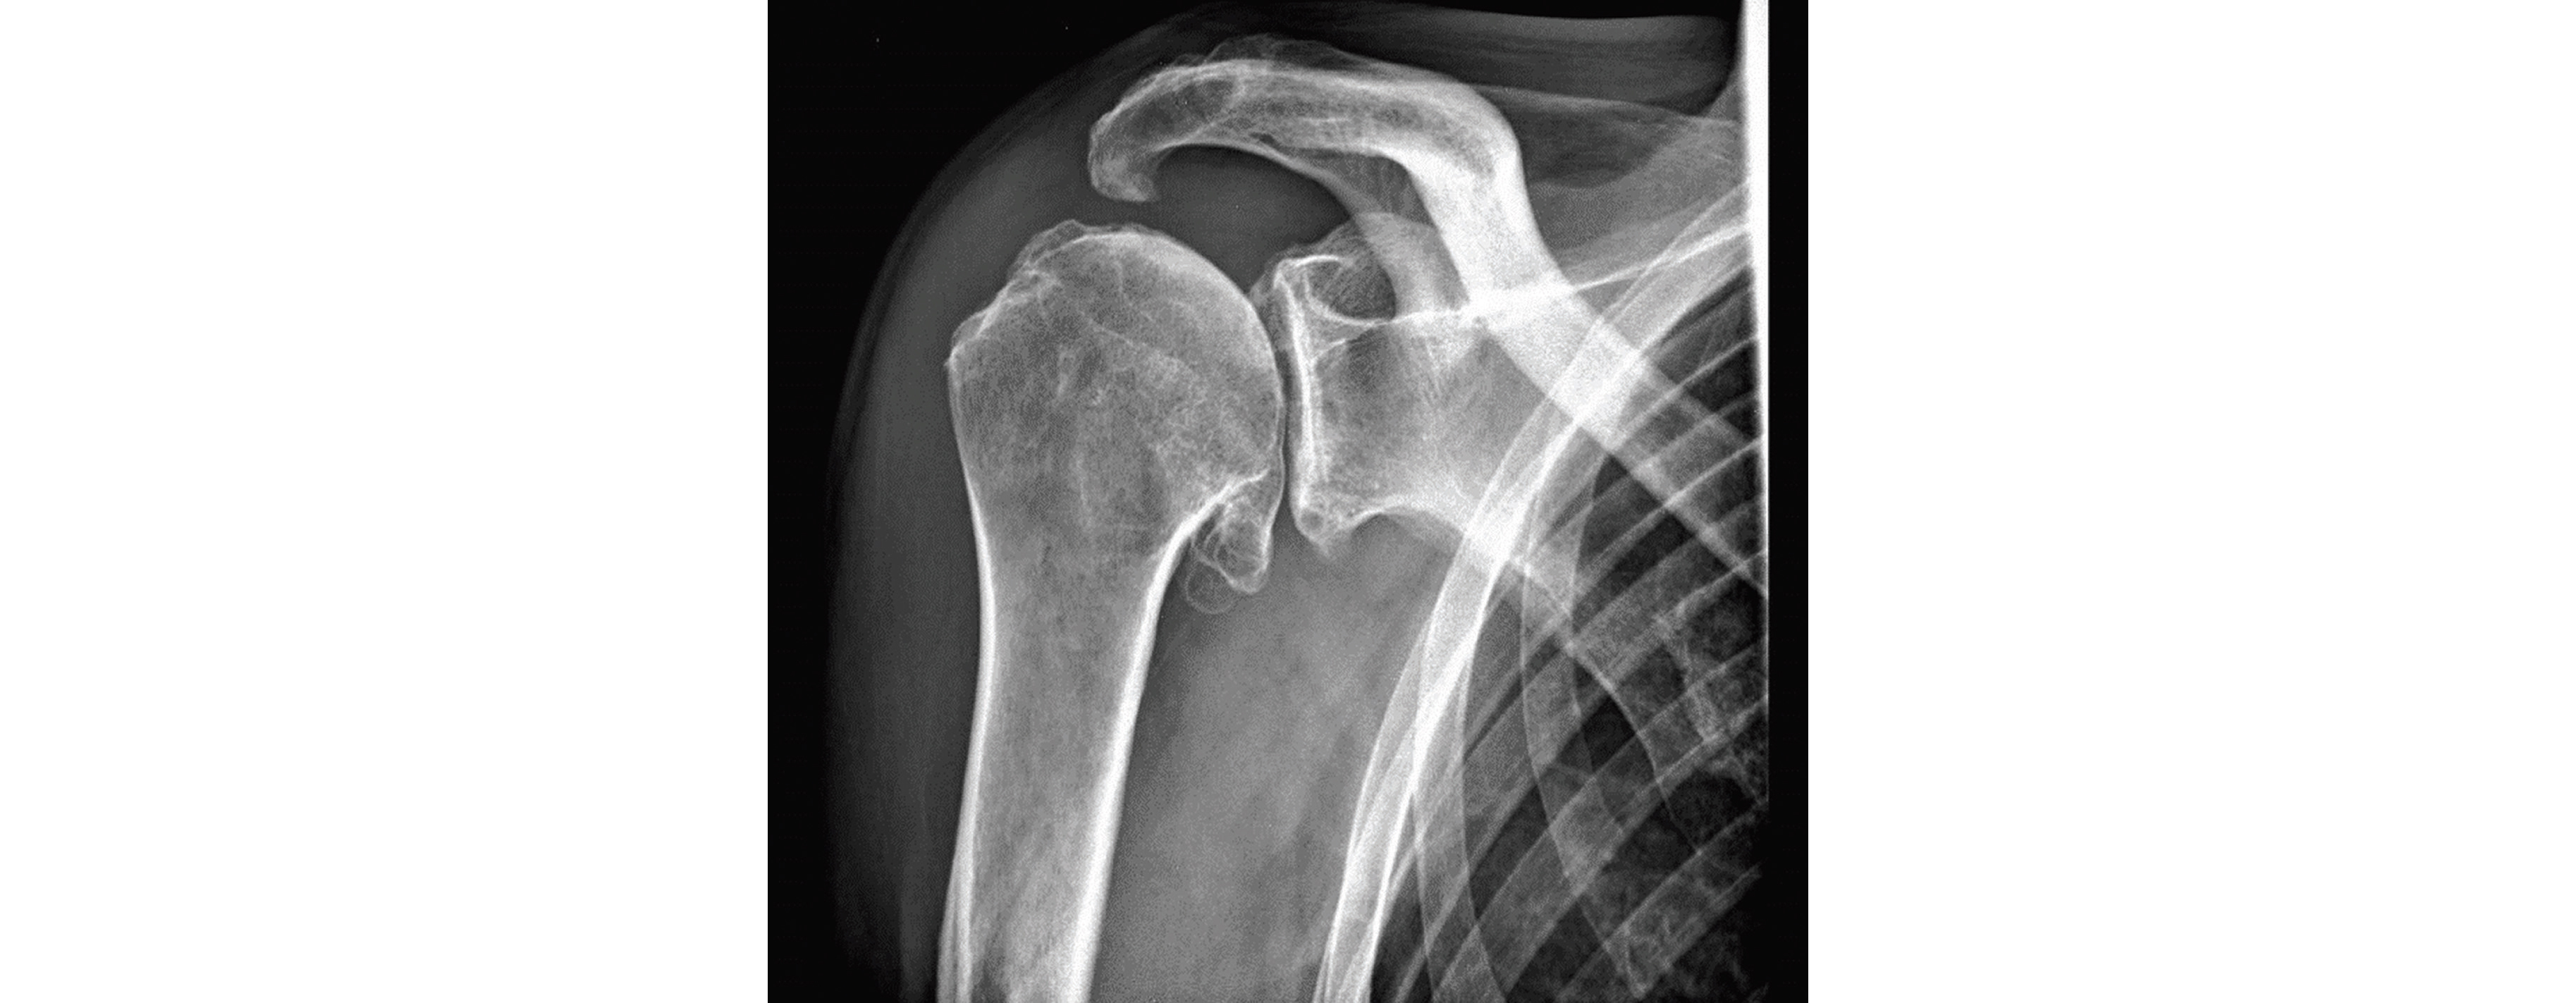

Douleur d'épaule sur omarthrose

Chez le sujet âgé par argument de fréquence, l'arthrose d'épaule sera le diagnostic le plus fréquent : on parlera alors souvent d'omarthrose ou arthrose de l'articulation gléno-humérale. Pour confirmer votre diagnostic vous demandez une radiographie d'épaule de face, de profil et en rotations neutre-interne-externe.

Dans le cas d'une capsulite rétractile cette radiographie sera sans anomalie, tandis que dans une omarthrose on retrouvera les signes de condensation de l'os sous-chondral, goutte ostéophytique, pincement gléno-huméral, géodes sous-chondrales. On décrit alors deux types d'omarthroses : centrée (ou primitive) et excentrée (ou secondaire) s'il existe une ascension de la tête humérale, une diminution de l'espace sous-acromial et une rupture du cintre gléno-huméral... Cette dernière est plus fréquente et est secondaire à une rupture de la coiffe des rotateurs.

Omarthrose chez un patient de 79 ans avec pincement articulaire, ostéophytose

et goutte ostéophytique inférieure, bec acromial